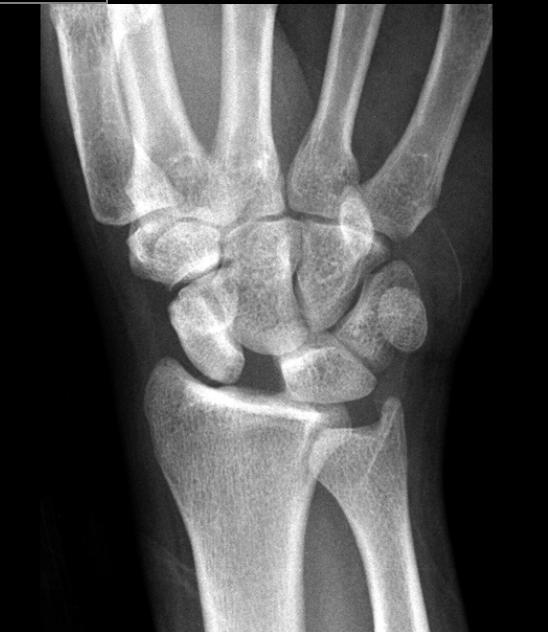

Welche Pathologie erkennen Sie auf folgendem Röntgenbild? Welche Bänder sind bei eben diese Pathologie gerissen?